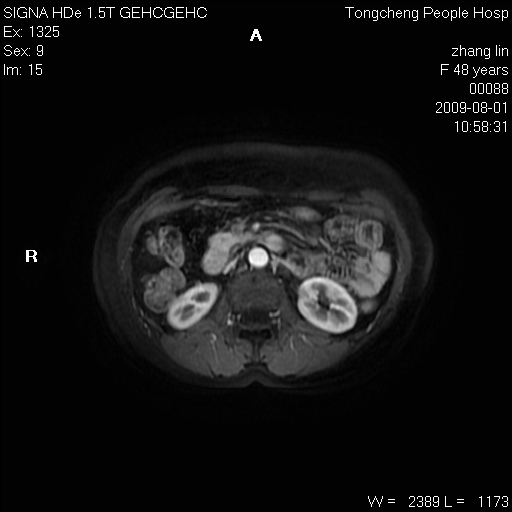

女,48岁。健康体检,彩超发现右肾占位性病变。平素健康。

临床诊断:右肾占位性病变,性质待定(囊肿?肿瘤?)。

上中腹部mr平扫+增强扫描,图像如下:

右肾上极见一类圆形病灶,t1wi呈等信号t2wi呈等高混杂信号,三期增强无强化,边界清---考虑囊肿出血。

同反相位均表现为等信号,病变无强化,考虑含蛋白的囊肿可能,弥散加权相或许有些帮助,